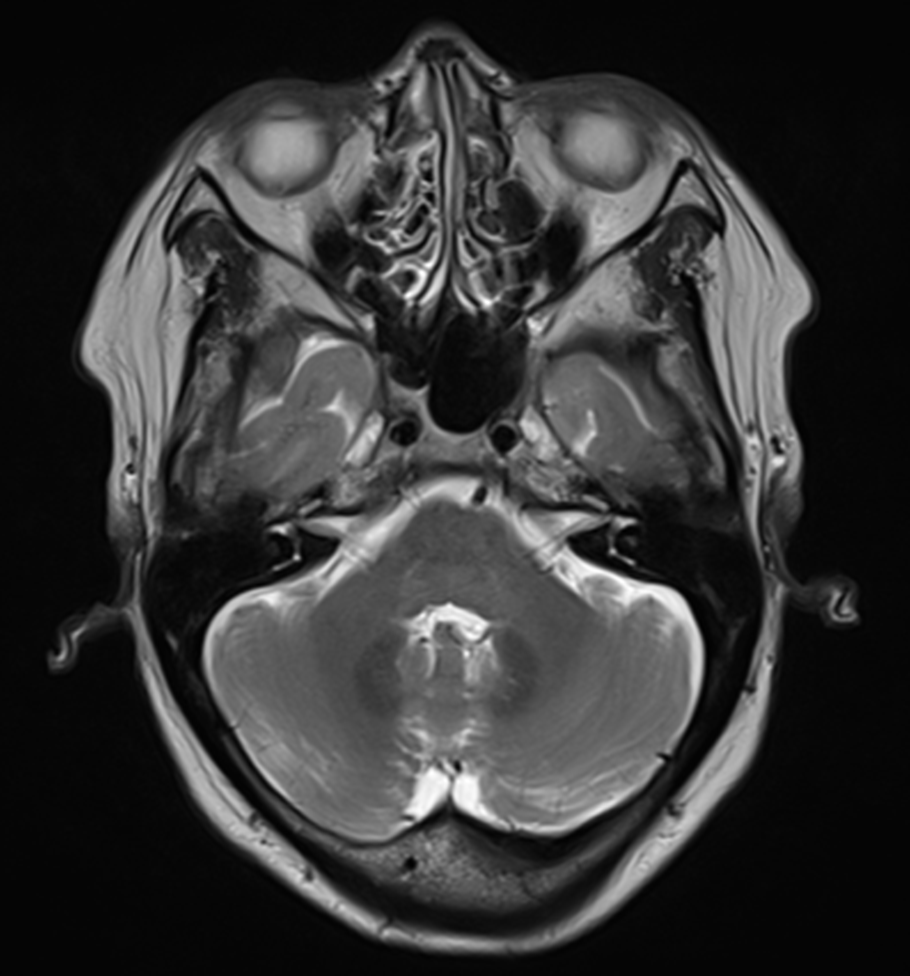

뇌 MRI로 확인한 정확한 원인

저희는 즉시 뇌 MRI 검사를 진행했습니다.

✅ 3차신경의 염증 상태 확인

✅ 신경 압박 여부 정밀 진단

✅ 다른 뇌 질환과의 감별 진단

이 목적에 있었죠. ㅎㅎ

검사 결과, 예상했던 대로

3차신경에 염증이 발생해 있었습니다.

그림9.png 촬영 일시: 2025.05.30

<Fig 1. Brain MRI>